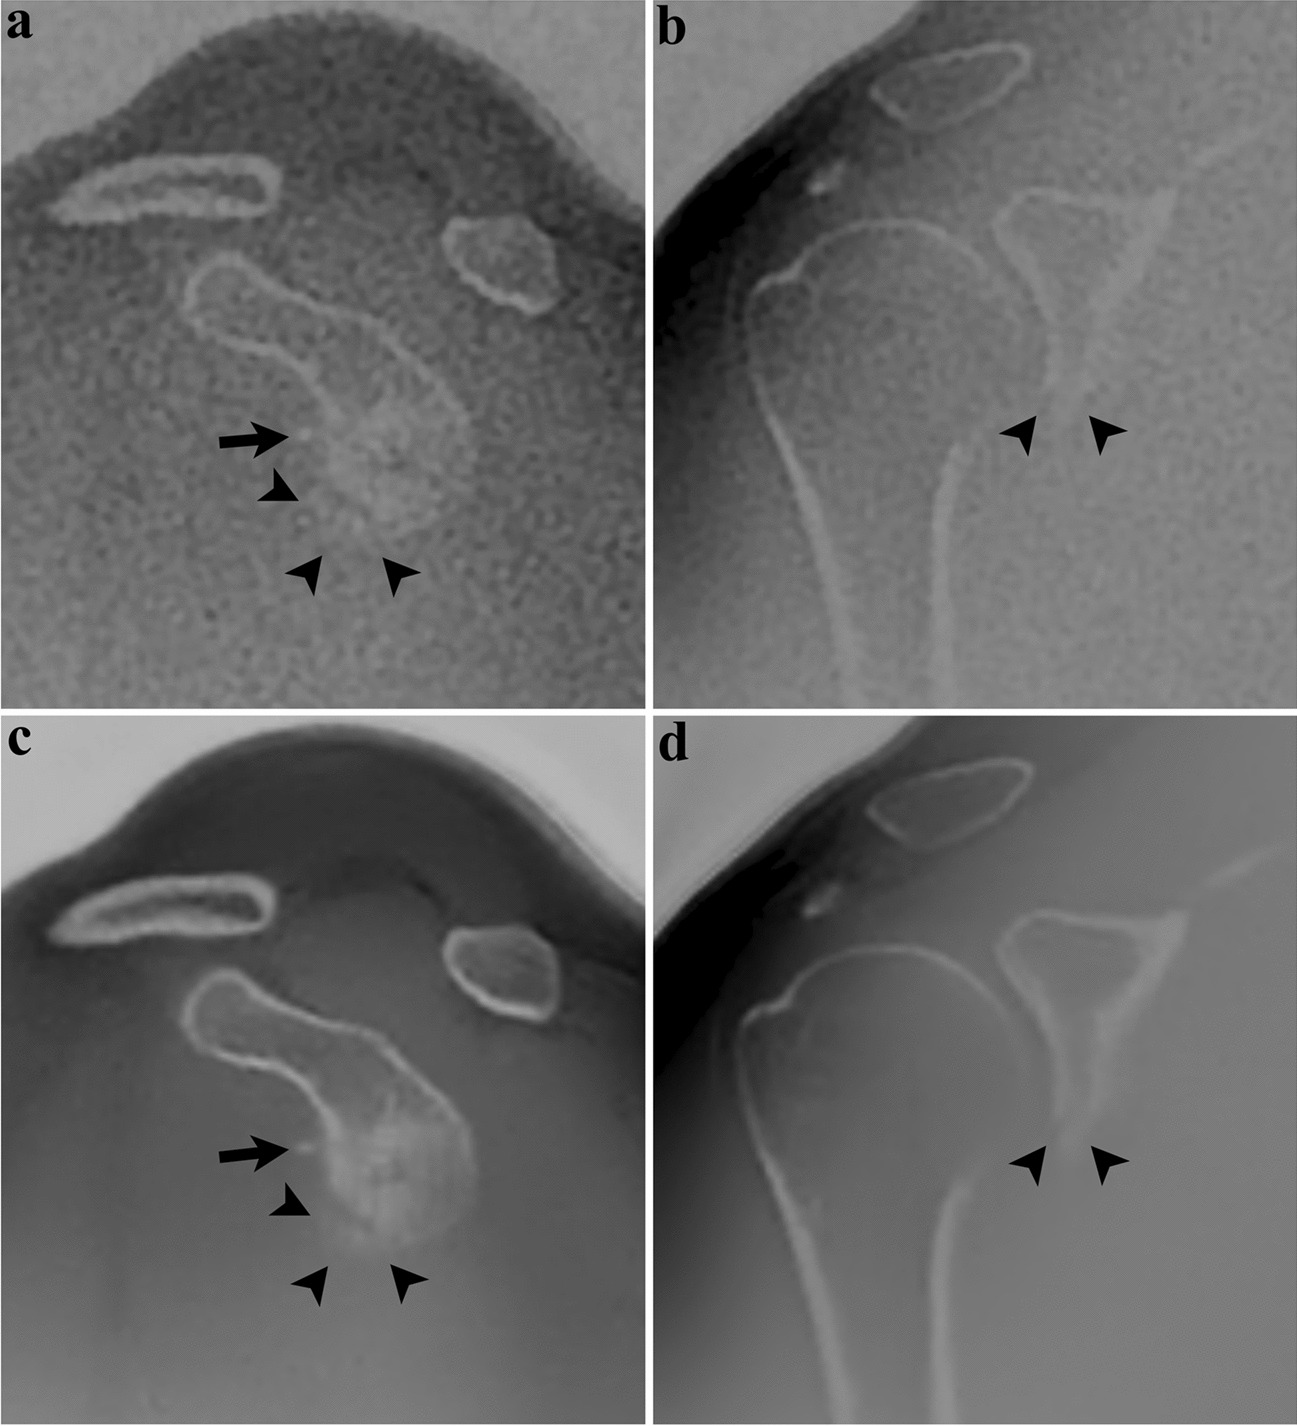

Delineation of fracture lines and fragments was significantly improved for DLRecon versus SOC (p ≤ 0.03) (Fig. 4). Diagnostic confidence in evaluating these fractures was also rated significantly higher in DLRecon images (p = 0.023).

Fig. 4

Thirty-nine-year-old man with a history of recurrent shoulder dislocations. Sagittal and coronal ZTE images processed using DLRecon (c, d) demonstrate improved delineation of the osseous Bankart lesion (arrowheads), compared to the SOC reconstruction method (a, b). Note the small additional osseous fragment anterosuperior to the glenoid (arrow)

Inter-rater agreement for delineation of fracture lines and fragments was substantial for both DLRecon (κ = 0.69 and 0.73) and SOC (κ = 0.76 and 0.63) (Fig. 6). Inter-rater agreement for diagnostic confidence in evaluating posttraumatic changes was substantial for DLRecon (κ = 0.71) and moderate for SOC (κ = 0.56).

Fig. 6

Sixty-seven-year-old woman presenting after shoulder dislocation. Sagittal (upper row) and axial (lower row) ZTE images demonstrate a Hill-Sachs lesion. DLRecon (b, d) improves visualization of the depressed cortical fragment (arrows), compared to SOC reconstruction (a, c). As a result, the exact extent of the lesion can be assessed with higher diagnostic certainty